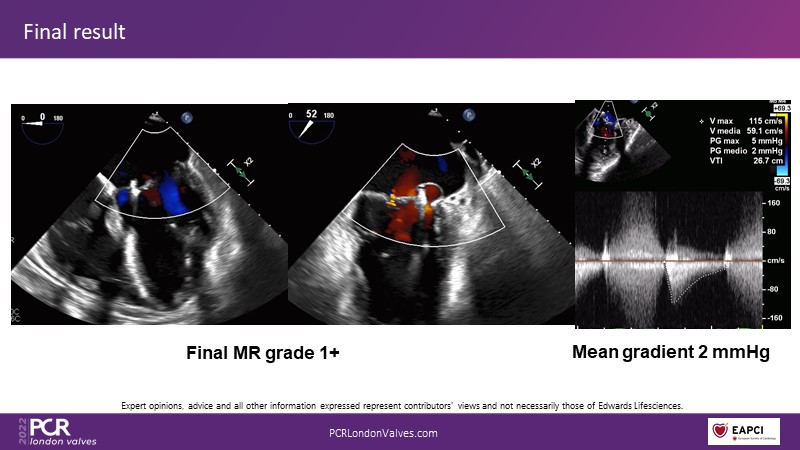

The new PASCAL Precision system unleashes the full potential of mitral transcatheter edge-to-edge repair

Join this panel of experienced physicians to learn more about the novel PASCAL Precision system and to discuss implant selection and clinical data. Finally, participate in a recorded case demonstrating the use of the PASCAL Precision system for the treatment of mitral regurgitation.